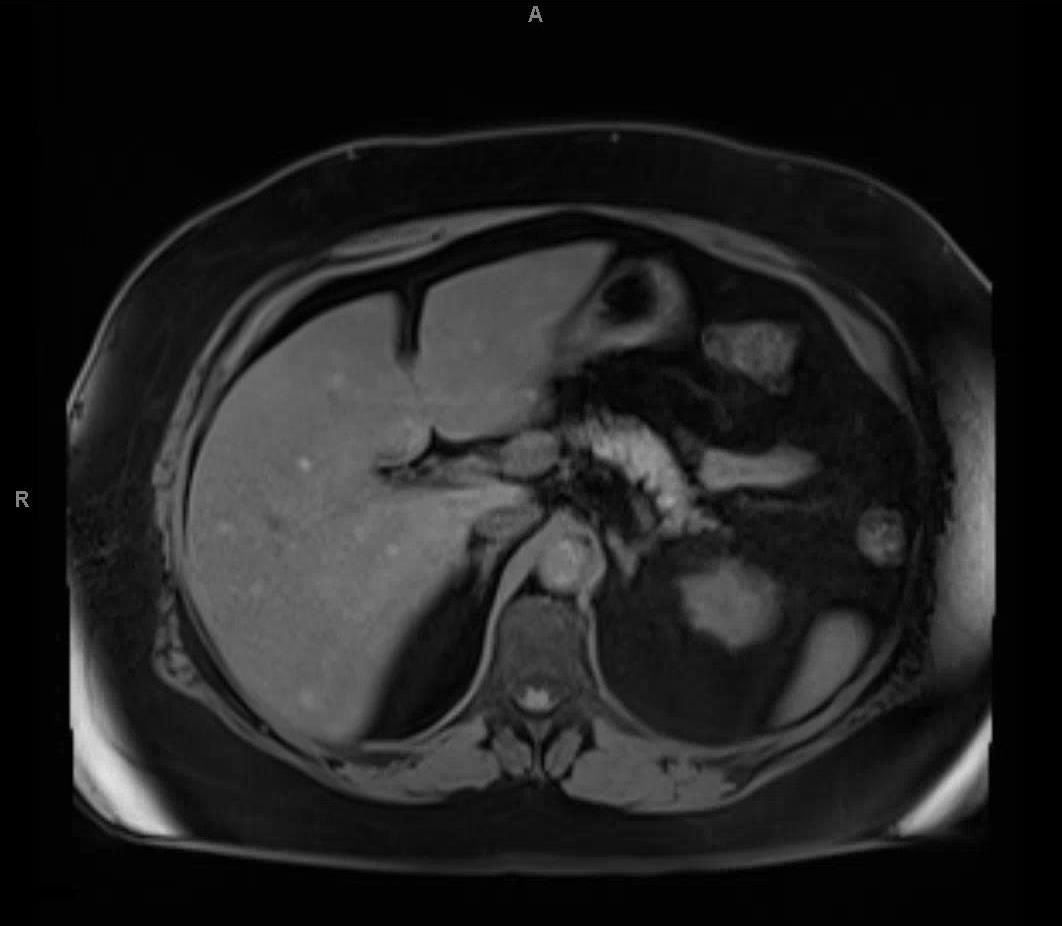

The patient underwent an abdominal ultrasound which revealed multiple hypoechoic lesions less than 1 cm dispersed throughout the liver (Figure 1). Magnetic resonance imaging was also performed and demonstrated multiple lesions dispersed throughout the liver (Figure 2). In addition, both imaging modalities showed a background of hepatic steatosis. Biopsy of a representative liver lesion demonstrated a malignant neoplasm infiltrating the hepatic parenchyma arranged primarily in a nested pattern (Figure 3). The neoplasm was composed of spindled and epithelioid cells with deep brown pigmentation within the cytoplasm (Figures 4 and 5). Given the morphologic findings, no immunohistochemical studies were performed.